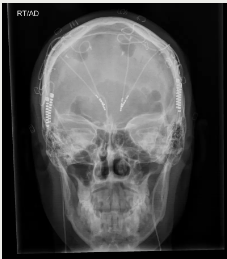

脑深部电刺激(DBS)使用电极激活神经回路。在这张大脑的扩散张量图像中,最亮的点表示植入物的位置

x射线图像显示了为治疗抑郁症而植入的两根DBS电极。

DEPARTMENT OF NEUROSURGERY, BAYLOR COLLEGE OF MEDICINE